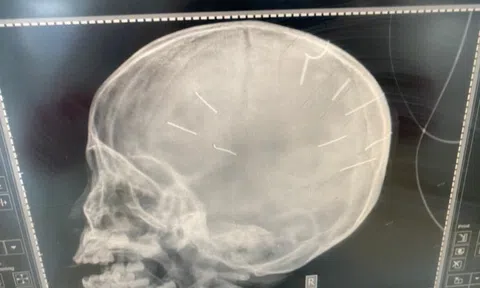

Rộ tin bé 3 tuổi bị đóng đinh vào đầu sắp được phẫu thuật rút đinh: Sự thật là gì?

Bé 3 tuổi tại Thạch Thất (Hà Nội) bị chính người tình của mẹ đóng đinh vào đầu vẫn đang được điều trị hồi sức tích cực tại Bệnh viện Xanh Pôn.

Mẹ bé gái 3 tuổi bị đóng đinh vào đầu: 'Em rất sốc, không thể ngờ Huyên làm vậy'

"Một đằng là con em, một đằng là người ăn ở với em. Em từng tin tưởng anh ta... Con em nó có tội gì đâu?...", mẹ đẻ bé Đ.N.A. đã chia sẻ như vậy về việc con bị hành hạ.